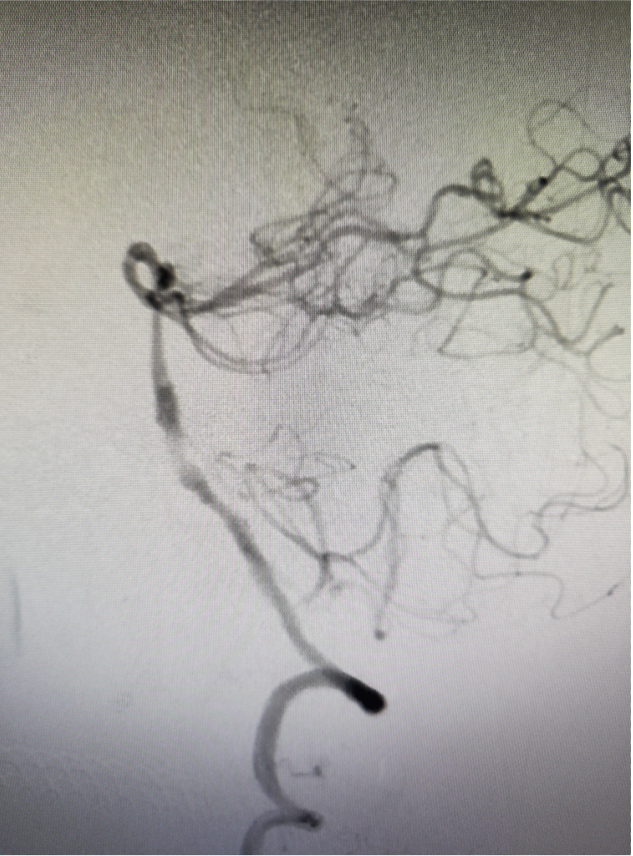

狭窄改善明显,前向血流维持良好,mTICI分级3级

该患者为原位狭窄,导丝导管通过困难,通路的顺利建立是本例病患手术成功的关键因素。

Locaste长鞘头端柔软,近端支撑力强。Skathi远端通路导管支撑力足够,系统稳定,操作顺畅,通过性好,远端亲水头手感丝滑,裸奔直接通过V3-4段,到达基底动脉狭窄近段轻松自如。狭窄部位狭窄程度较重,通过困难,逐步球扩后置入支架,Skathi远端通路导管极其稳定,通过球囊、支架系统顺利,可为进一步的安全治疗奠定基础。